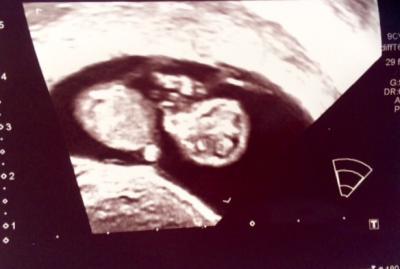

Gestern waren wir beim Gyn und unserem Gummibärchen geht es prächtig Es hat fleißig geturnt. Mutti und Vatti sind ganz verliebt und total happy Wir wurden vordatiert um 6 Tage. Das heißt am Wochenende erreichen wir die 12ssw. Es ist schon stolze 3,65 cm groß. Wobei die erste Messung bei 3,8cm lag. Find ich persönlich ja schöner ;) In 2 Wochen dürfen wir wieder hin, dann wird das erste große Screening gemacht. Davor haben wir beiden schon nen bissl Bammel Bis dahin versuchen wir positiv zu denken :) Liebste Grüße de Kiri

Bild zu 😍 das kleine Wunder wächst und ist putzmunter 😍 - Forum für Januar - Mamis